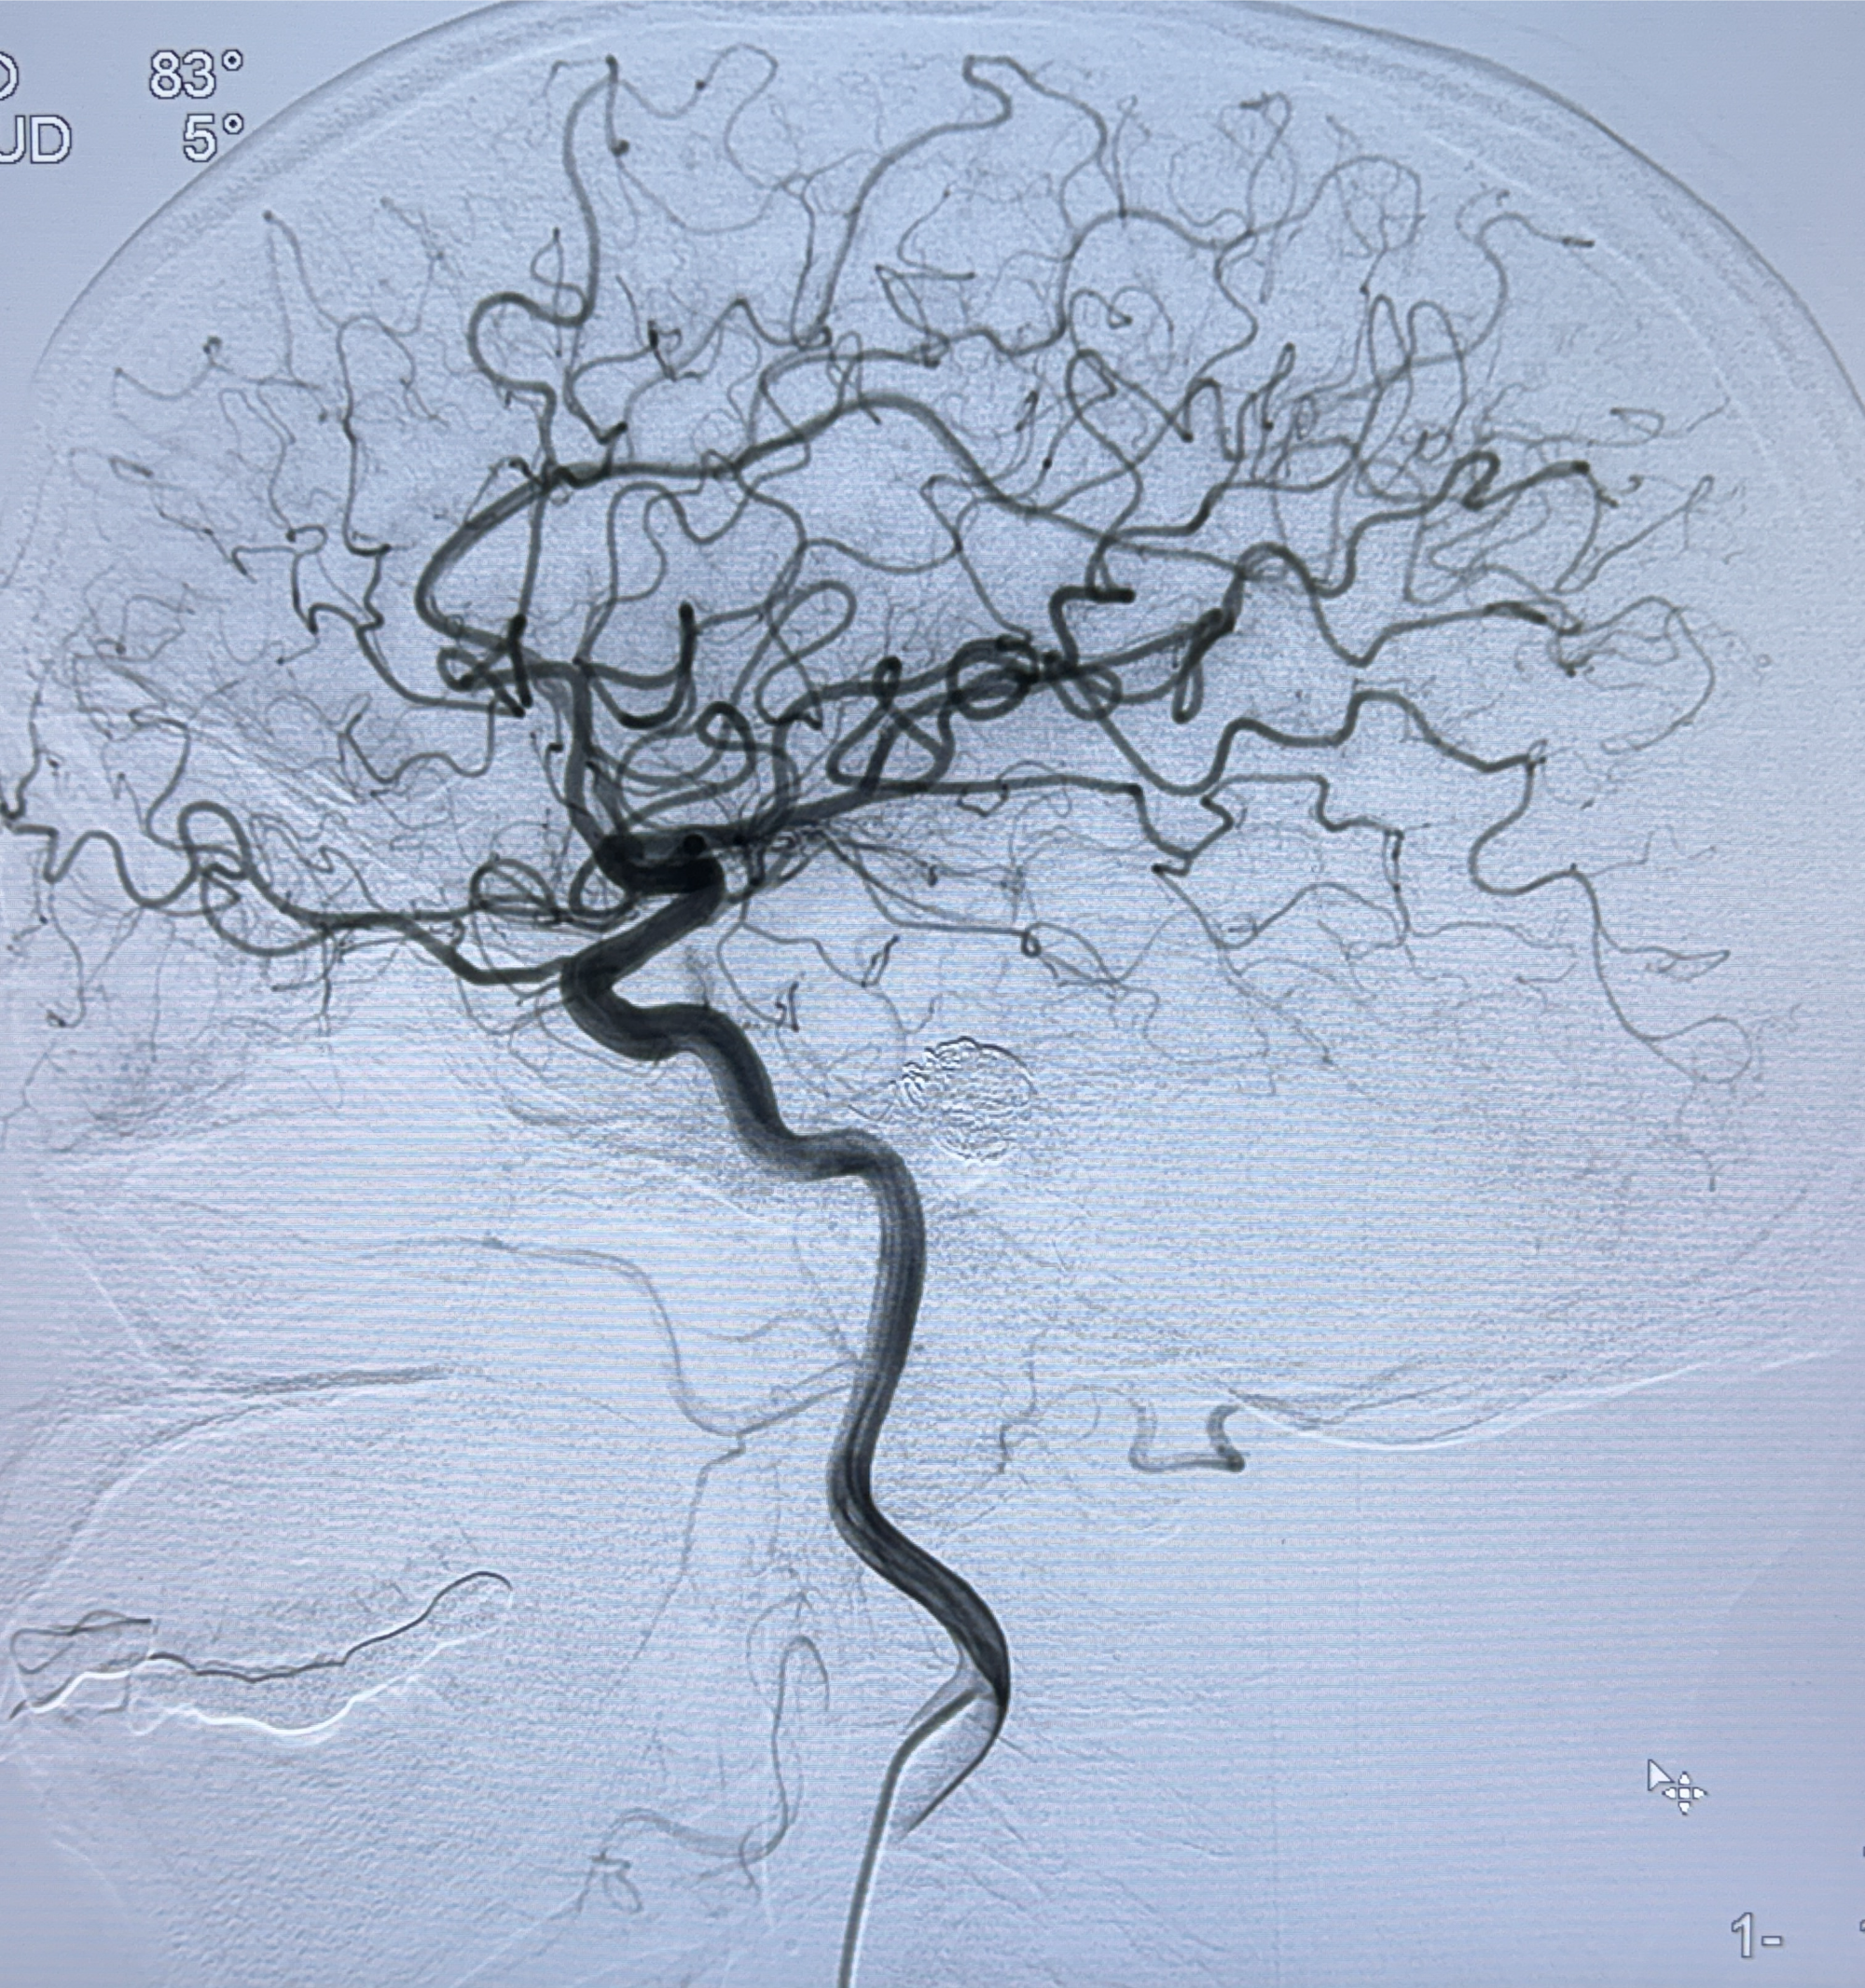

2024-01-08DSA:右侧椎动脉V4段夹层动脉瘤双支架辅助弹簧圈栓塞术后

患者支架辅助治疗后18个月,动脉瘤痊愈